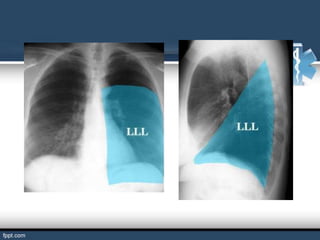

BRONQUIOS SEGMENTARIOS

Son ramificaciones de los bronquios lobulares.

El hombre tiene 18 bronquios segmentarios que estos se ramifican

en bronquiolos.

Si los bronquios segmentarios ya no se puede subdividir se le llama

bronquiolo terminal.